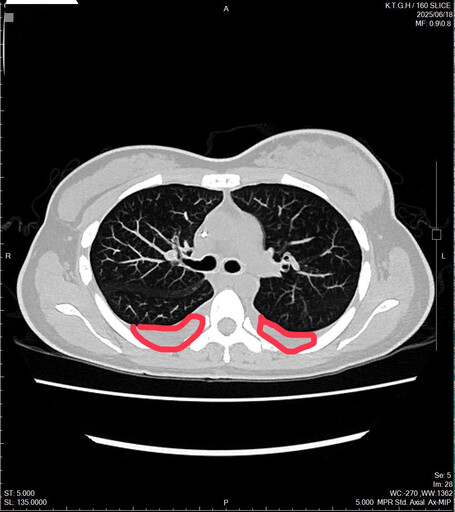

一位來自北部的林小姐,長期輪大夜班、作息不規律,直至2023年5月在自我檢查時發現乳房有硬塊,起初未立即就醫,直到腫塊逐漸變大,才前往醫院檢查。確診時,已罹患乳癌第四期,且癌細胞已轉移至骨骼、肺部與腹部,甚至造成雙側肺積水和呼吸困難,病情比她想像中更為嚴重。

林小姐確診時,已罹患乳癌第四期,且癌細胞已轉移至骨骼與肺部,甚至造成雙側肺積水。